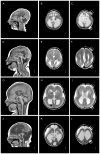

Lissencephaly ("smooth brain," LIS) is a malformation of cortical development associated with deficient neuronal migration and abnormal formation of cerebral convolutions or gyri. The LIS spectrum includes agyria, pachygyria, and subcortical band heterotopia. Our first classification of LIS and subcortical band heterotopia (SBH) was developed to distinguish between the first two genetic causes of LIS-LIS1 (PAFAH1B1) and DCX. However, progress in molecular genetics has led to identification of 19 LIS-associated genes, leaving the existing classification system insufficient to distinguish the increasingly diverse patterns of LIS. To address this challenge, we reviewed clinical, imaging and molecular data on 188 patients with LIS-SBH ascertained during the last 5 years, and reviewed selected archival data on another ∼1,400 patients. Using these data plus published reports, we constructed a new imaging based classification system with 21 recognizable patterns that reliably predict the most likely causative genes. These patterns do not correlate consistently with the clinical outcome, leading us to also develop a new scale useful for predicting clinical severity and outcome. Taken together, our work provides new tools that should prove useful for clinical management and genetic counselling of patients with LIS-SBH (imaging and severity based classifications), and guidance for prioritizing and interpreting genetic testing results (imaging based- classification).